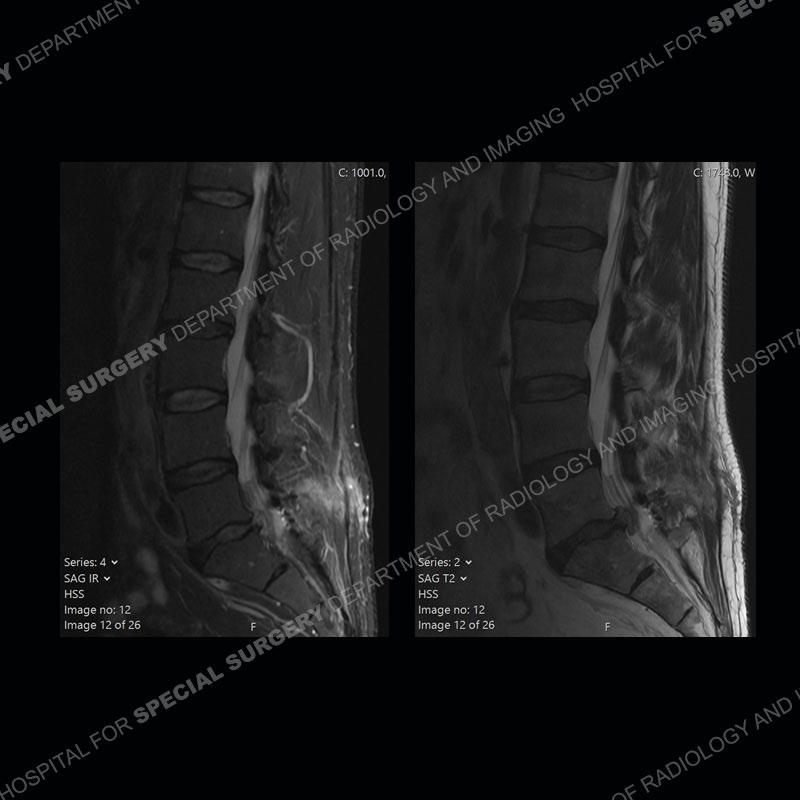

Post operative changes are seen on the left side at L5-S1 where there is near complete removal of the left sided L5 lamina, partial resection of the left L5-S1 facet joint, and resection of the left sided ligamentum flavum. In the anterolateral epidural space about the subarticular recess is a mass that demonstrates similar T1 and T2 signal characteristics to the adjacent degenerated disc. There is enhancement about the periphery of the mass, but the majority of this somewhat geographic or polyploid mass demonstrates no enhancement. The mass exerts prominent mass effect on the left S1 axillary sleeve/proximal nerve root. The left S1 nerve root shows enlargement and increased enhancement as compared to the contralateral right side.

Diagnosis: Recurrent Disc Herniation

Not as much of a diagnostic dilemma as some other cases but more so just a very nice example of what can be a difficult assessment at times. The evaluation of granulation tissue/scar/epidural fibrosis vs. disc herniation particularly in the earlier post operative period can be very difficult. Clues that can assist in identifying a disc herniation are a more geographic or polypoid nature to the mass, signal characteristics similar to the adjacent degenerated disc, mass effect upon the thecal sac/adjacent neural structures, and a typical enhancement pattern. As the disc material is avascular, as long as imaging is performed in a relatively rapid fashion after contrast administration (within 20-30 minutes), the granulation tissue around the disc will enhance but the disc material itself will not. If there is a marked delay between contrast administration and imaging, there may be diffusion of contrast into the disc making the assessment very difficult. The marked utility of contrast to help delineate disc vs. scar has led to our institution employing contrast fairly uniformly within the first two years following surgery.

The scar tissue in the setting of prior disc removal will be present in the anterior and anteriorlateral aspect of the epidural space. The signal characteristics can be somewhat variable from slightly more T2 hyperintense earlier on to T2 hypointense as the scar matures. However, the signal does not tend to follow the adjacent degenerated disc. The scar can produce mass effect, but it does not have to do so. In addition, at times the scar may be associated with a retraction of the adjacent thecal sac. Given the vascular nature of the scar there is typically somewhat avid, uniform enhancement which occurs fairly rapidly after contrast administration and begins to diminish within 20 minutes or so. Trying to discern the difference between scar and disc is of paramount importance given the rather poor outcomes associated with resection of scar as compared to disc material.